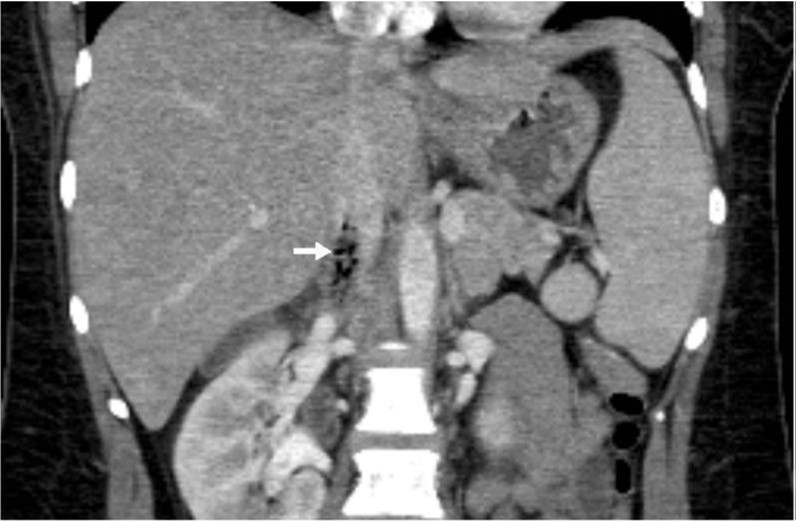

Fig. 1. A

Fig. 1. Enhanced axial and coronal CT scan shows thrombus with air-bubbles in IVC adjacent to duodenal second portion.

Fig. 1. B